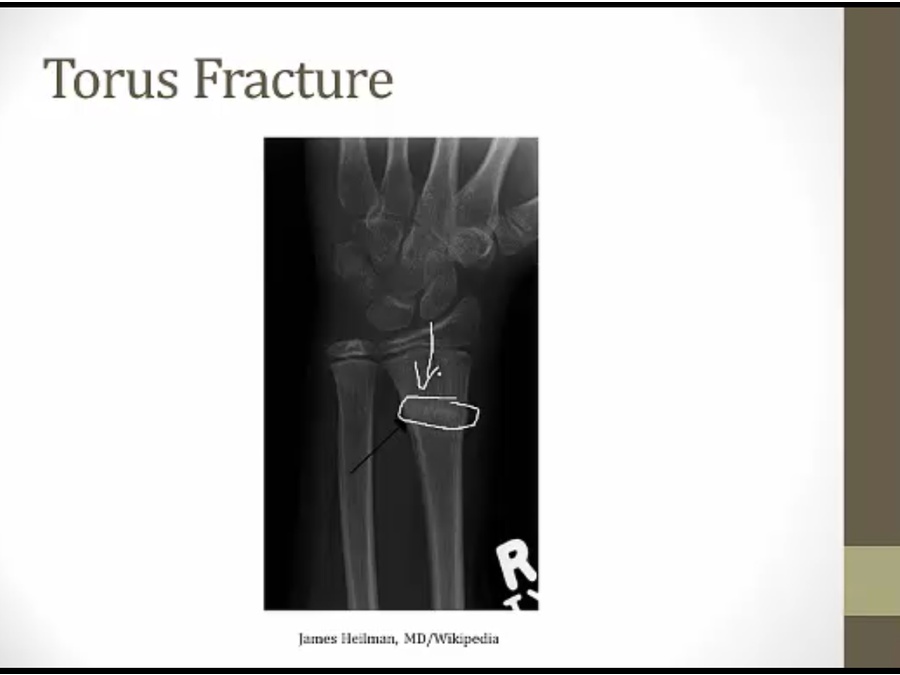

Pediatric

children have softer bones

bone doesn't completely snap in two

Torus